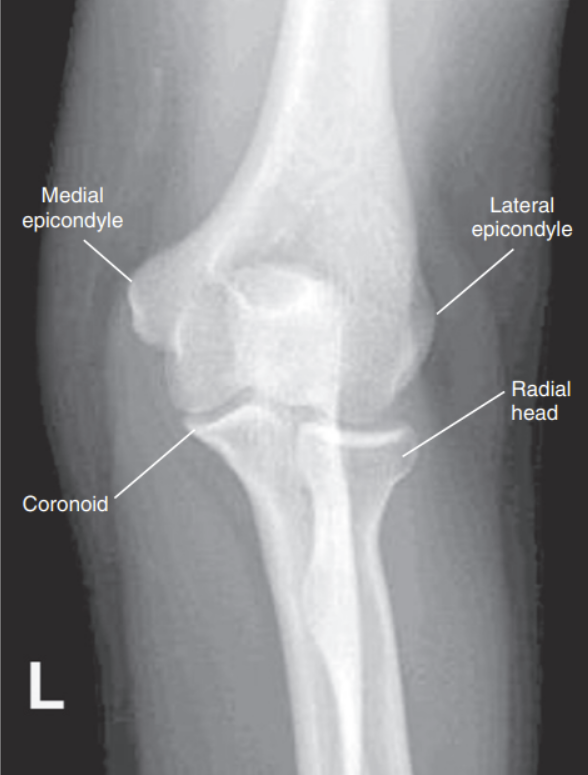

What is wrong with this external oblique elbow?

Superimposition of proximal tib/fib

Obliquity is less than 45 degrees, meaning its under-rotated

Radius and ulna are not superimposed, but coronoid can be seen

Over-rotation with obliquity of more than 45 degrees

the distal capitulum surface is demonstrated too far distal to the distal surface of the medial trochlea and the radial head is placed too far posteriorly to the coronoid process

Proximal humerus is elevated

Distal capitulum is too far proximal to the distal medial trochlear surface of the radial head is too far anterior to the coronoid process

Distal forearm is depressed